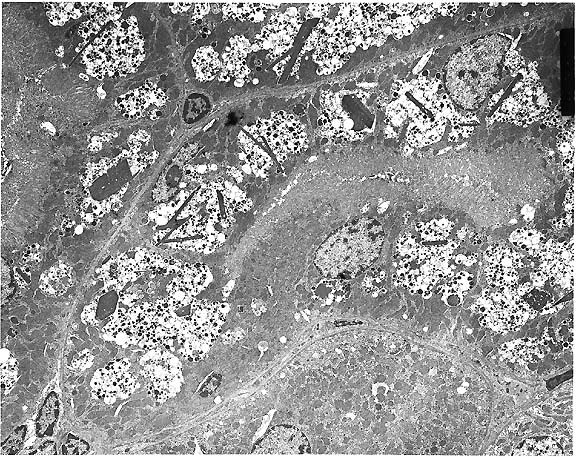

- Case 12-3. Eye. As described below.

- Gross Pathology: An irregularly shaped, pale tan mass

measuring approximately 0.75 cm in diameter was present within

the globe and extended caudally from the iris.

- Contributor's Diagnosis and Comments: Eye: Iridociliary

adenocarcinoma.

- A partially encapsulated, highly cellular mass consisting

of cuboidal to polygonal cells arranged in loose cords, packets,

and occasional rosettes is adherent to the posterior aspect of

the iris and to the ciliary body. The neoplasm infiltrates the

base of the iris and extends into the filtration angle. Irregularly

shaped, dilated channels are present in some areas, and the mass

is supported by a fine fibrovascular stroma. Cells within the

mass have large, round to oval, occasionally indented nuclei,

1-2 nucleoli, finely stippled chromatin, small to moderate amount

of foamy, eosinophilic cytoplasm, and variably-distinct to indistinct

cell margins. A few cells have large, irregularly shaped nuclei,

and the mitotic rate varies from 0-3 per high-powered field.

Some scleral vessels adjacent to the neoplasm contain thrombi

and seemingly have "infiltrates" of cells (may not

be visible in all sections); the cells are dissimilar to those

within the neoplasm and may, in fact, represent a reaction to

thrombosis or other negative vascular events.

2x

obj

- Case 12-3. Eye. A monomorphic mass replaces the iris.

40x

- Case 12-3. Ocular tumor. Sheets of pleomorphic polygonal

cells occasionally palisade around a central lumen (pseudorosette

formation).

- AFIP Diagnosis: Eye: Ciliary body adenocarcinoma,

Domestic Longhair, feline.

- Conference Note: This neoplasm was studied in consultation

with the Department of Ophthalmic Pathology. Conference participants

agreed with the contributor's diagnosis. An expansile, infiltrative,

densely cellular neoplasm has effaced the ciliary body and is

composed of polygonal cells arranged in packets, nests, tubular

structures, and pseudorosettes, supported by a fine fibrovascular

stroma. Neoplastic cells have significant atypia, with occasional

bizarre cells. The mitotic rate is high. Scattered within the

tumor are entrapped melanophages which contain moderate amounts

of brown-black granular to globular pigment.